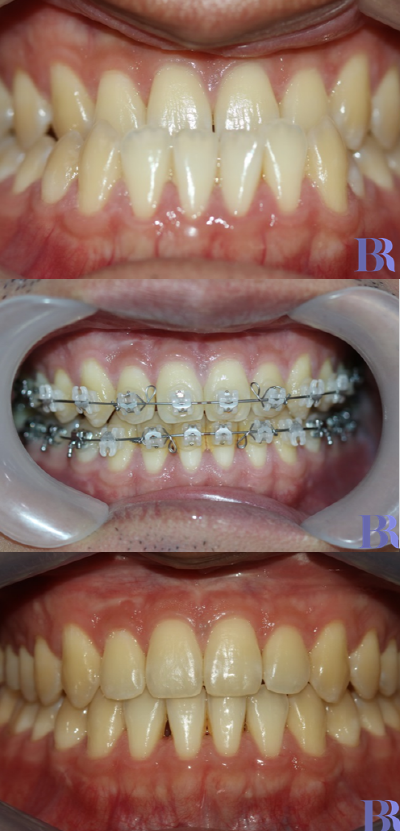

초진 입안사진입니다

치아가 거꾸로 물리고 있으나

실제 골격이 나온것에 비해서는

덜 나와 보이네요.

양악수술 대상자의 전형적인

치아 상태를 볼수 있습니다.

치성보상작용으로 인해

실제 골격에 비해 치아 간격이

좁아 보입니다

아랫니와 윗니 앞뒤 차이가

외모에 비해 심하지는 않습니다

치료 종료 후 입안을

촬영한 사진입니다

심미적일 뿐만 아니라

초진 시 보다 훨씬 더

건강해 보이지 않나요?

초진->수술직후->치료종료후

초진->수술직후->치료완료후

구내사진입니다.

정말 치료가 잘되었죠?

양악수술 전후 변화를

한눈에 보실 수 있습니다.